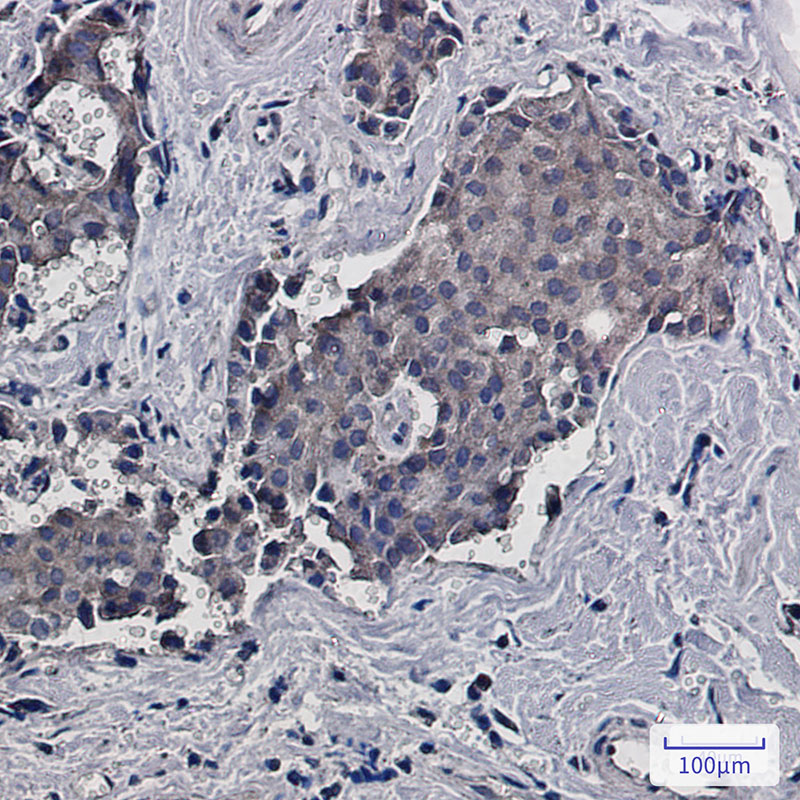

IHC 1/50-1/100 Human,Mouse,Rat